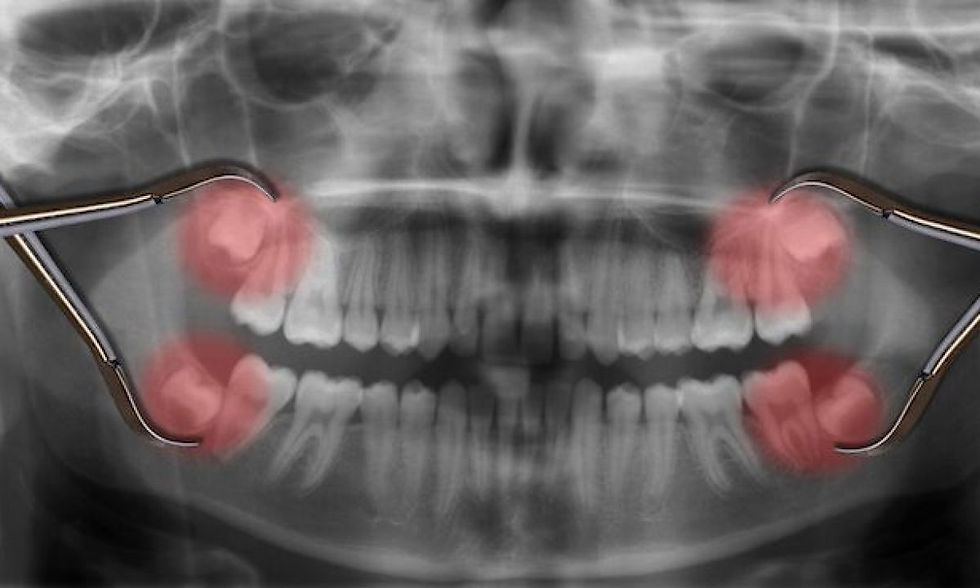

Tomografía y Escáner 3D

Cirugía guiada